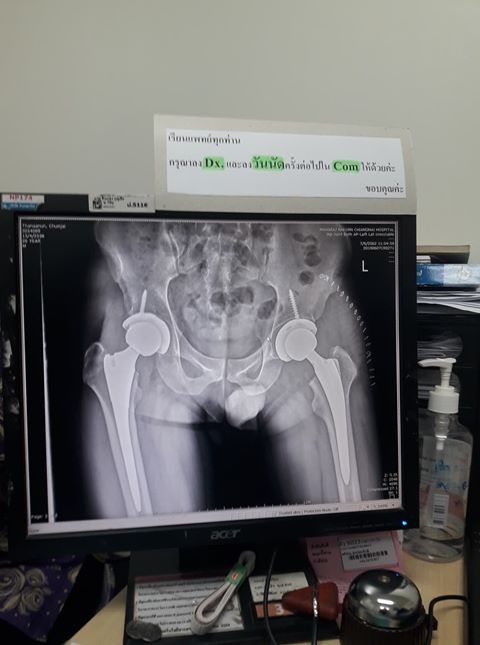

ทหารหนุ่มแชร์ประสบการณ์ วิ่งสู้โรค SLE แต่ได้โรคกลับมาเพิ่ม ป่วยหัวกระดูกข้อสะโพกตายจากการขาดเลือด ต้องผ่าตัดเปลี่ยนข้อสะโพกทั้งสองข้าง ไม่สามารถวิ่งได้อีกตลอดชีวิต

อย่างไรก็ตาม ตนวิ่งได้ไม่ถึงปี ก็มีอาการปวดสะโพกอย่างมาก เมื่อไปตรวจก็พบว่ามีภาวะหัวกระดูกข้อสะโพกตายจากการขาดเลือด (Avascular necrosis) หรือโรค AVN ซึ่งเป็นผลมาจากการรับประทานยากลุ่มสเตียรอยด์ในการรักษาโรค SLE สุดท้ายจึงต้องผ่าเปลี่ยนข้อสะโพกทั้งสองข้าง และไม่สามารถวิ่งได้อีกตลอดชีวิต